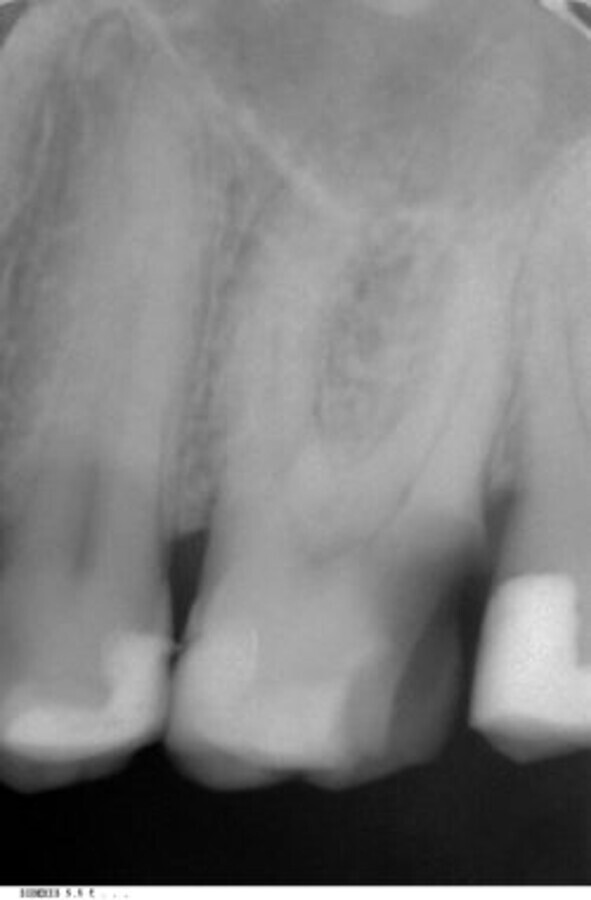

Fig. 7: Radiographic follow-up after two years.

After two years and as part of follow-up, the radiographic check confirmed the reliability of the obturation (Fig. 7). The situation in the root canals was unchanged and the patient was evidently still free of complaints. In the past year, that is six years after treatment of the tooth, a further recall image again showed no abnormalities or changes to the final findings (Fig. 8). The long-term prognosis seems to be pleasingly positive despite the strong curve of the mesial root.